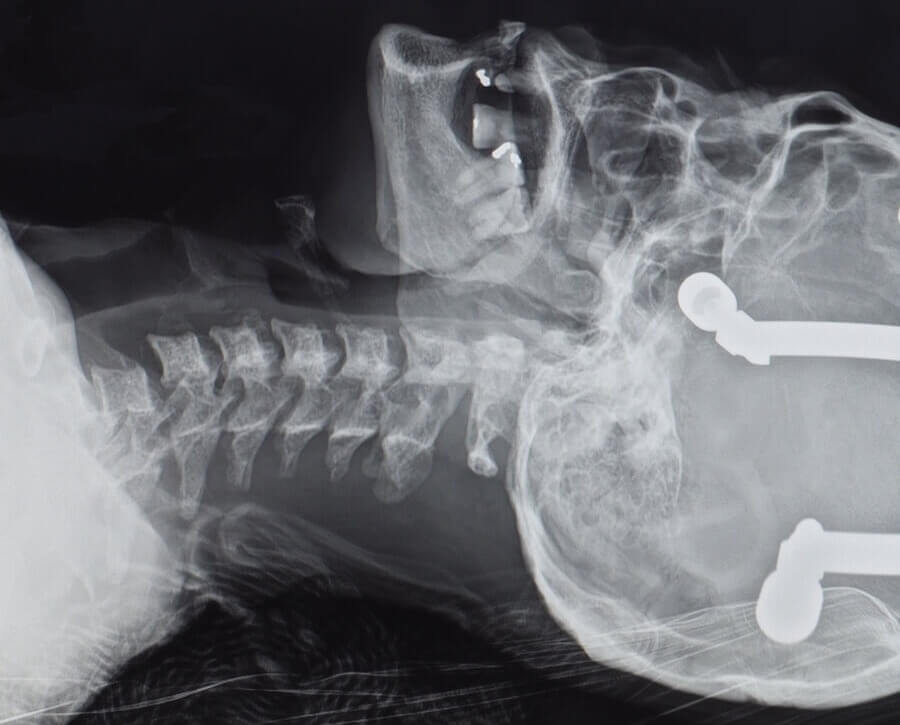

Calgary Injury Law Accident Requiring Surgery Neck Pain Concussion Can A Concussion Cause Neck Pain Many people have neck pain after a concussion or whiplash injury. What can cause neck pain the most common causes of neck pain are: That pain may involve stiffness,. This forceful movement can be caused by a violent blow to the head and. During a concussion, the brain slides back and forth against the inner walls of the skull. The. Can A Concussion Cause Neck Pain.